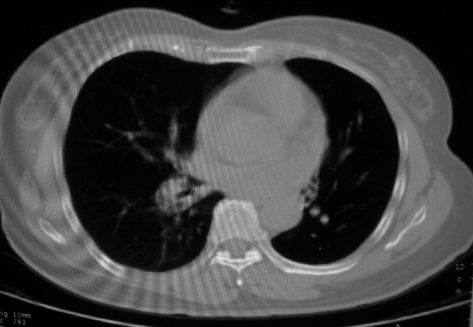

以下是引用李衡钧在2008-7-24 14:24:00的发言:[br]左侧胸廓变小,左肺上叶见大面积致密阴影,其内有空洞及不规则钙化。上纵隔略向左移位,上肺胸膜增厚。左肺门及纵隔淋巴结增大。右肺见散在的致密结节影。[br]印象:继发性肺结核。